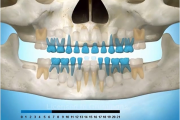

Esimeste molaaride (purihammaste) lõikumine. 1. molaaride ektoopilise lõikumise jälgimine. Ülemised ja alumised esimesed purihambad e. molaarid lõikuvad orienteeruvalt6-7-aastaselt piimahammaste rea lõppu. Enamasti lõikuvad samanimelised jäävhambad paaridena. Normaalne lõikumise Loe edasi »